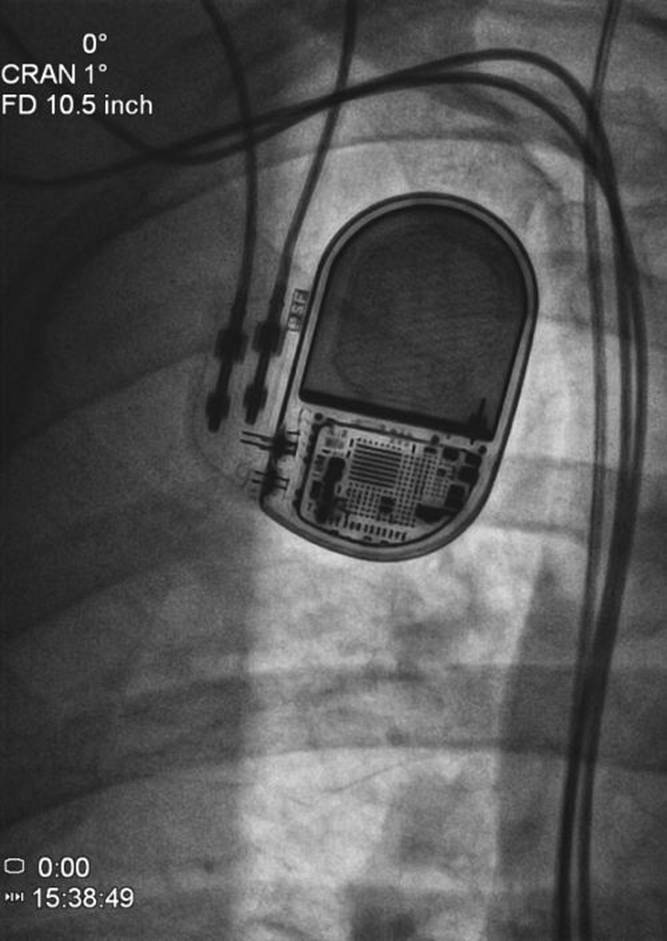

新規のPMは、メーカーを変える。MRI(magnetic resonance imaging=磁気共鳴映像法)対応でドイツ製とのこと(国内では駄目)。サイズは従来のものより大きいというので、皮膚に負担が掛かると、感染の原因となるのではと。感染しないことが、大切ですからと、先生。

ペースメーカーは、BIOTRONIK社製、エヴィア(Evia DR-T電池寿命14年)に替わった。ホームモニターリングをし、ドイツにあるセンターへPMのロギングデータを夜中に毎日送る。MRIにも耐えるということだが、日本では承認されていない。